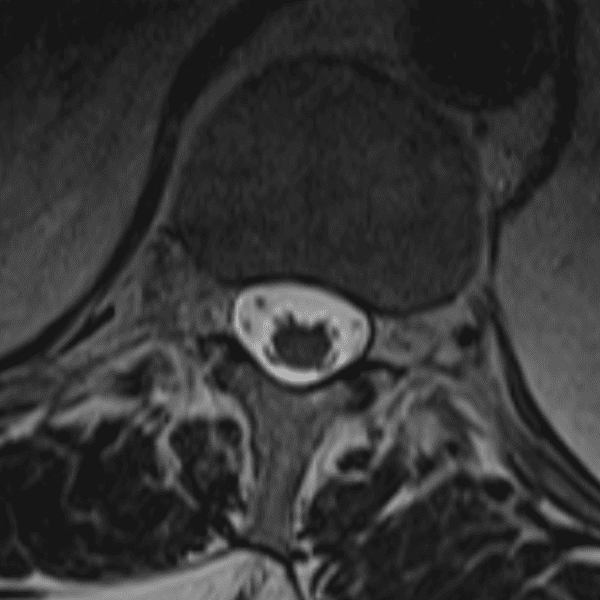

Simulates call by including subtle or difficult cases and some normals.

35 cases